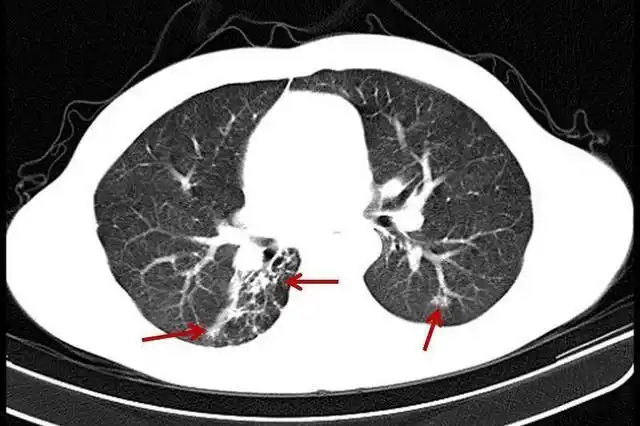

义诊先行 学术护航 关注肺间质纤维化 共享呼吸健康_医疗_疾病_特发性

图文丨无原因的杀手之肺囊性纤维化(上)

肺纤维化

头条问答 - 双肺多发纤维化钙化灶,会出现什么问题?(14个回答)